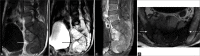

Figure 14:

(a-c) Contrast MRI pelvis. Expansile pelvic mass centred at the sacrococcygeal junction showing a low to intermediate T1-weighted signal with presence of T1-weighted hyperintense foci indicating intralesional haemorrhage or proteinaceous contents high T2-weighted signal on fat-saturation images and moderate heterogeneous contrast enhancement. (d) Contrast MRI pelvis. Preserved intervening fat plane with the rectum anteriorly (white arrow). Focal breaching of tumour capsule invading into subcutaneous fat posteriorly (black arrow).